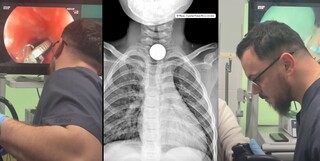

Під час обстеження рентген-знімок показав, що монета перебувала у верхньому відділі стравоходу, в ділянці входу до нього.

Такий стан є потенційно небезпечним і потребує негайного медичного втручання.